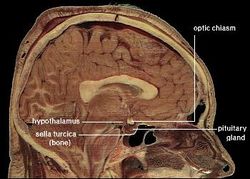

الوطاء hypothalamus يربط الجهاز العصبي بجهاز الغدد الصم عبر الغدة النخامية (hypophysis). الوطاء hypothalamus, (من الكلمة اليونانية ὑποθαλαμος = تحت ثلاموس thalamus) تقع تحت المهاد thalamus, مباشرة فوق جذع الدماغ brain stem. وهذه الغدة تحتل الجزء الأعظم من المنطقة البطنانية ventral من الدماغ البيني diencephalon. وتوجد في أدمغة جميع الثدييات. وفي البشر, يبلغ حجمها تقريباً نفس حجم اللوزة. وتسمى تحت المهاد و هي منطقة صغيرة موجودة في قاع الدماغ تؤدي دوراً رئيسياً في تنظيم المستوى العام لنشاط الجسم ويطلق عليها أيضًا الوطاء أو الهايبوتلاموس. ويساعد تحت المهاد على التحكم في الجهاز العصبي التلقائي، وهو أحد أجزاء الجهاز العصبي الذي ينظم عمليات الجسم اللاإرادية مثل التنفس ومعدل ضربات القلب. كذلك يتحكم تحت المهاد في الغدة النخامية المسماه الغدة الرئيسية لجهاز الغدد الصماء المنتجة للهورمون.